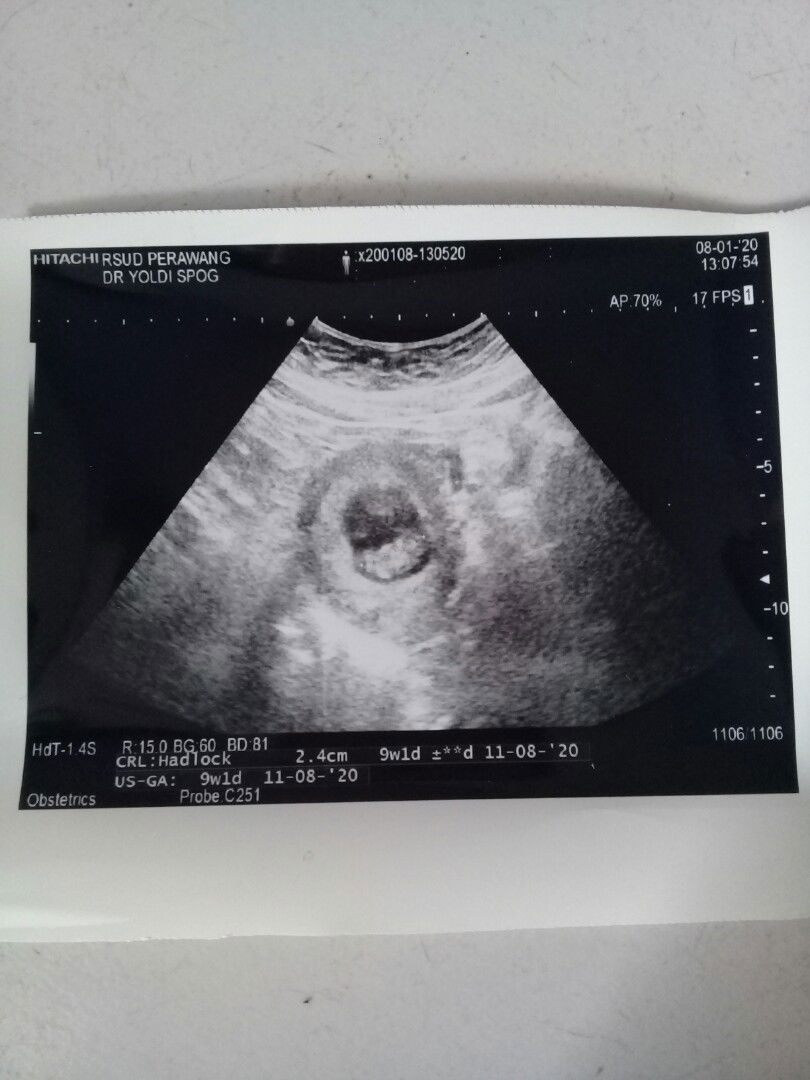

HPL agustus 2020

Ada yang sama ga hpl agustus 2020❤

aq Bun hpl bidan 26agust,hpl USG 27 Agustus

31 juli-03 agustus.. itu mnrt hpht dan usg

Di TAP 5 agustus. Di bdan dn USG 7 agustus

31 juli mnurut hpht 11 agustus mnurut usg

Usg pertama 22 juli dan kedua 8 agsts😊